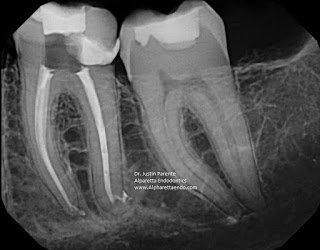

Sometimes, as in this #19 below, the exit can be found at the apex in the form of a sharp distal turn or delta. Direct instrumentation may or may not be possible with small, pre-bent files (6 or 8).